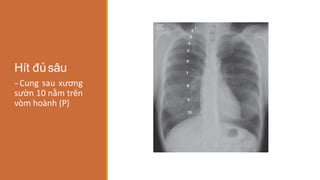

Hít đủsâu

‐Cung sau xương

sườn 10 nằm trên

vòm hoành (P)